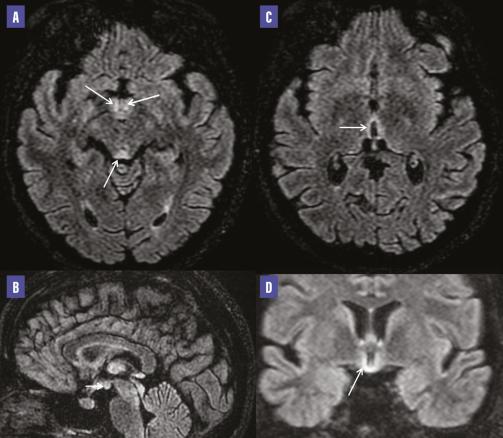

Une patiente âgée de 23 ans, sans antécédents pathologiques notables, enceinte à cinq semaines d’aménorrhée, se plaint de vomissements gravidiques incoercibles sans prise en charge adéquate. Elle est adressée au service des urgences pour une symptomatologie neurologique caractérisée par un syndrome confusionnel. L’examen révèle une amnésie, un syndrome cérébelleux statique et un nystagmus. Le bilan biologique montre une alcalose métabolique avec hypokaliémie, alors que la ponction lombaire est normale. Un scanner cérébral est réalisé en urgence et ne montre aucune anomalie. Le lendemain de son admission, la patiente bénéficie d’une imagerie par résonance magnétique (IRM) cérébrale, qui met en évidence un hypersignal sur les séquences pondérées en FLAIR/T2, symétrique et bilatéral au niveau périaqueducal, des corps mamillaires, et autour du troisième ventricule sans restriction en diffusion et sans rehaussement pathologique après injection de gadolinium (figure ). Ces éléments sont très évocateurs, dans ce contexte clinique, d’une encéphalopathie de Gayet-Wernicke. L’administration parentérale de 1 g de vitamine B1 par jour, conjointement avec de la vitamine B6, est initiée, puis remplacée par une administration orale de vitamine B1 à raison de 500 mg deux fois par jour jusqu’à la fin de la grossesse. Deux mois plus tard, une amélioration significative du syndrome cérébelleux et des troubles mnésiques est observée.

Les anomalies associées à l’encéphalopathie de Gayet-Wernicke sont généralement bilatérales et symétriques, localisées en périaqueducales, au niveau de la paroi du troisième ventricule, en regard des corps mamillaires et des thalami médians. Des manifestations moins courantes peuvent également se produire dans des zones telles que le vermis cérébelleux supérieur, les noyaux des nerfs crâniens, le noyau rouge, le noyau dentelé, le splénium, ou même corticales. Sur le plan radiologique, le scanner est souvent normal ou peut montrer des zones d’hypodensité. En revanche, l’IRM révèle des lésions en hyposignal en pondération T1, en hypersignal en pondération T2 et FLAIR. De plus, un rehaussement pathologique est observé après l’injection de contraste en pondération T1. Quoique pathognomonique de cette pathologie, le rehaussement intense des corps mamillaires est rarement observé. Les anomalies peuvent présenter un signal hyperintense en diffusion, bien que le coefficient apparent de diffusion puisse varier.2